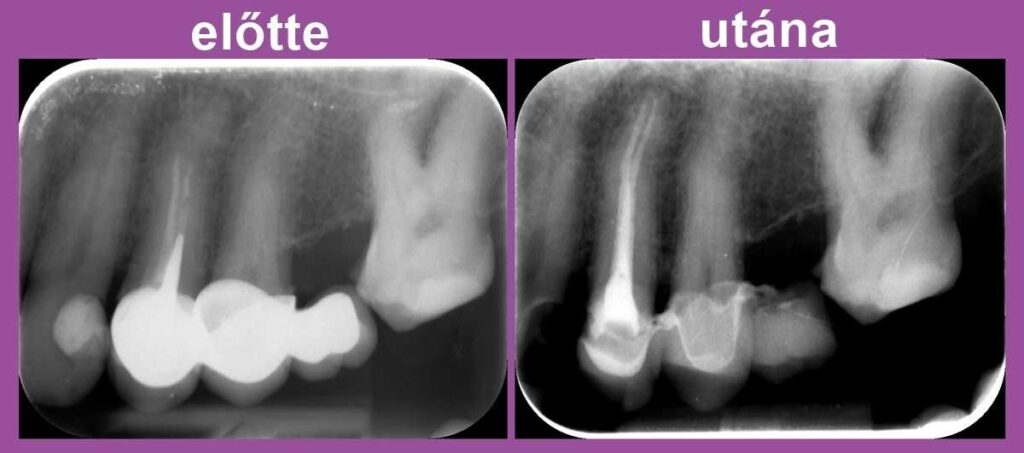

Dr. Molnár Katalin páciense a bal felső fogaknál jelentkező tompa fájdalomra panaszkodva érkezett fogászatunkra. A panorámaröntgent követően készítettünk kisfelvételt is az érintett oldalról.

A képen látható, hogy a bal felső négyes fog a híd alatt csappal van megerősítve, és a gyökértömés a csatornákban nem ér végig. Ennek következtében a gyökércsúcs körül gyulladás alakult ki. Nyilvánvalóvá vált, hogy a híd levételére, a csap és a gyökértömés mikroszkóppal történő eltávolítására lesz szükség.

A második alkalommal a csatornák újabb fertőtlenítésére, tisztítására került sor. Ezek után elkészült az új gyökértömés, melyhez ismét igénybe vettük a mikroszkóp segítségét.

A fog panaszmentessé vált – így hát megmenekült attól, hogy el kelljen távolítani!